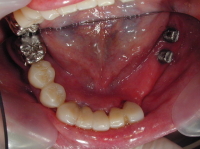

治療例を下記写真に示します。上あごは総入れ歯で下の部分入れ歯は非常に収まりの悪いものでした。左下奥歯の保存が難しいため抜歯をし、残っている歯も古い冠を撤去し土台から再治療させていただきました。歯周病が中等度の進行状況でしたので将来のリスク管理を考え固定式のブリッジではなく取り外しのできる タイプの入れ歯で対応しました。しかし左下奥歯が一本もないのでかみ合わせの力配分を考慮(右側だけの片咀嚼を避けるため)し、左下奥にインプラントを植立 (左側 上から4番目の写真です)し、右側の歯の負担を減らした設計としました。

写真は左側が「治療前」、右側が「治療後」です。